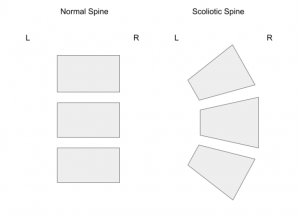

Children and teenagers who have scoliosis will notice that these changes impact their posture and how they move. Normally, the bones in the spine are rectangular and are evenly spaced from side to side. Children and teens who have scoliosis will have at least three bones in their spine that are larger on one side than the other. This is what contributes to the shape of the spine.